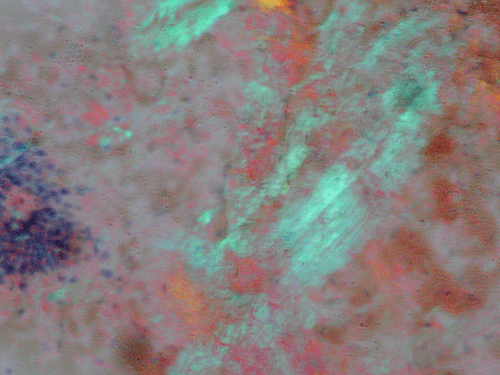

Clumps of amorphous substances with hypocellularity are noted with DiffQuick stain (arrows in Panel A) and Papanicolaou stain (arrows in Panel B). Normal glandular structures are also seen these preparations (Panel A and B). These amorphous substance stains orange on Congo red stain (Panel C and E) which gives a birefrigence under polarized light (Panel  D and F are corresponding images of Panel C and E). No tumor tissue is identified.

Amyloidosis is a broad designation for diseases characterized by the extracellular deposition and accumulation of amyloid. Amyloid is an insoluble protein with characteristic properties. It appears as non-branching fibrils with an average diameter of 10-12 nm. At the molecular level, the protein molecules arrange in a beta-pleated sheet conformation. This beta-pleated sheet is responsible for the distinctive apple green birefringence with Congo red stain 1. With routine hematoxylin-eosin stain, amyloid appears as pale eosinophilic, amorphous, extracellular deposition 1, 2.

Primary amyloidosis tends to involve the heart, gastrointestinal tract, nerves, skin, tongue, eye, and respiratory system. Secondary amyloidosis tends to involve the kidneys, liver, spleen, lymph nodes, adrenals, and thyroid. Symptomatic amyloidosis of the head and neck is a rare but well documented condition  3, 4, 5, 6, 7. Most cases in this region involve one organ, without evidence of generalized involvement. The cytologic diagnosis of unexpected amyloidosis in the head and neck region can be challenging. Amyloid can be misinterpreted as keratin debris, colloid, chondroid or basement membrane material. Salivary gland amyloidosis is most often secondary and can mimic Sjogren’s syndrome and also pleomorphic adenoma because of the amorphous appearance of amyloid. Amyloidosis involving the major salivary gland in the form of a mass is rather uncommon and often present as diffuse or focal, bilateral enlargement of salivary glands. Variable amounts of acellular, eosinophilic extracellular material stains pale red with Congo red stain, and exhibits a characteristic apple-green birefringence under polarized light. The remainder of the smear is often hypocellular, with scant or absent acinar cells, and scattered clusters of ductal epithelial cells such as are seen in chronic sialadenitis.